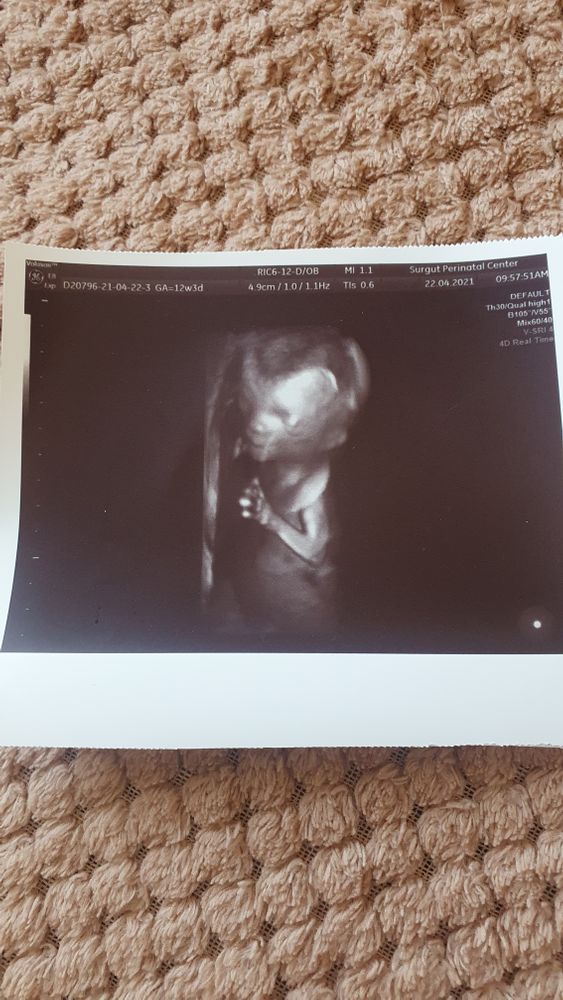

1 скрининк УЗИ ТВП

какая фотография у Вас четкая) мне даже на втором скрининге норм не смогли сделать . поздравляю и пусть все будет хорошо

Вики, мне в первую тоже такие фото не давали) хотя там же сейчас прохожу, от врача зависит, это она в 3д сделала)

Валентина, у меня второй уже был скринингг и таких четких фото не получилось )

Да, ТВП выше нормы, что не очень хорошо, но такое действительно бывает, особенно если КТР большой (а он явно большой, если вам 13,3 срок поставили). Что делать ? Ждать биохимию, можно параллельно НИПТ, если финансы позволяют. Если нет, ждать биохимию, и от этого плясать. При высоких рисках прокол, при низких - экспертное узи чуть позже.

Minou, ктр 73,4 и узист сказала, что крупный плод. Результат крови узнаю в сб, вот думаю все же подождать два дня и дальше смотреть